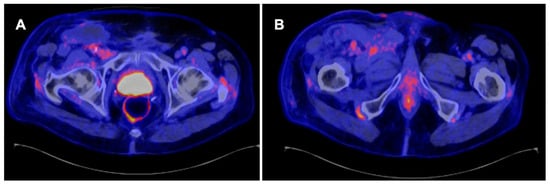

3.5. Role of PET CT in Follow-Up after Treatment

Local or nodal recurrences usually occur within 2–3 years of primary treatment. This suggests a rigorous follow-up schedule for the first two years, followed by less intense follow-up for at least five years [4,11]. Current guidelines recommend that PET/CT may be an alternative to CT or MRI for imaging follow-up after definitive treatment [4,36], as shown in Figure 3. In comparison to other imaging tests, PET/CT is usually more costly, and its availability may be a limiting factor in some countries [37]. Another drawback of PET/CT for systemic staging is that it is frequently conducted without intravenous contrast, which makes measuring the extent of visceral metastases difficult [24].

Figure 3. A 71-year-old man with stage pT1 pN1 penile squamous cell carcinoma shows no evidence of positive pelvic lymph nodes (A) or inguinal lymph nodes (B) during follow-up.